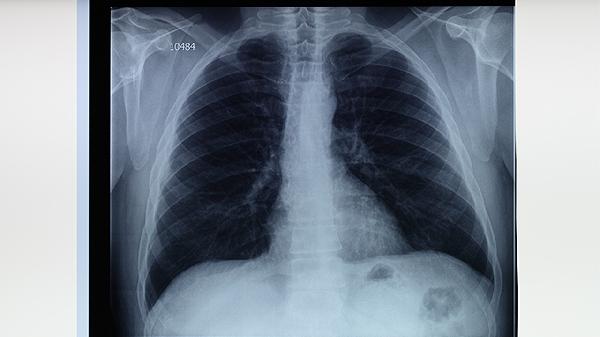

肺结核未及时控制可能经血行播散至全身,形成肺外结核。脊柱结核可导致背部放射性疼痛,结核性脑膜炎引发头痛,肠结核引起腹痛。这类疼痛多伴随低热、盗汗等结核中毒症状,需通过影像学检查确诊后调整抗结核方案,如加用吡嗪酰胺片或乙胺丁醇片。